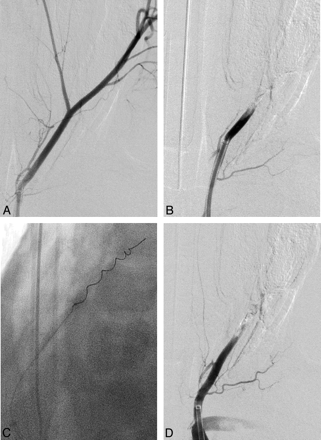

A total of 16 vessels (6 LAs, 8 SCAs, and 2 IMAXs) were occluded, and 48 retrieval attempts were made. A total of 8 vessels were successfully occluded with erythrocyte-rich clot (group A), and 8 vessels were occluded with fibrin-rich clot (group B). The Table summarizes the data and statistical significance between the 2 groups. In every target vessel, microcatheterization through the occlusion site was successfully achieved. Fourteen retrieval attempts were made to achieve the final angiographic results in the target arteries in group A, whereas 34 attempts were made in group B (P < .001). Every target vessel (100%) in group A achieved recanalization of TIMI grade 2 or greater, whereas only 3 of 8 vessels (37.5%) achieved recanalization of TIMI grade 2 or greater in group B. Figures 2 and 3 show the typical angiographic findings from each group. The average number of retrieval attempts to achieve the angiographic end point was 2.75 times in group A and 4.5 times in group B (P < .001). In group A, 3 vessels demonstrated TIMI grade 3 recanalization with 1 retrieval attempt, 2 vessels showed TIMI grade 3 recanalization after 2 attempts, 2 vessels achieved TIMI grade 2 recanalization after 2 attempts, and 1 vessel showed TIMI grade 2 recanalization after 3 attempts. In group B, 1 vessel achieved TIMI 3 recanalization after 2 attempts, 1 vessel achieved TIMI 2 recanalization after 3 attempts, and 1 vessel achieved TIMI grade 2 recanalization after 4 attempts. The remaining 5 target vessels in group B did not demonstrate significant vessel recanalization (1 vessel with TIMI 1 after 5 attempts and 4 vessels with TIMI 0 after 5 attempts) (Fig 2).

The average time required to achieve the final angiographic result was 15.5 minutes in group A and 81.5 minutes in group B (P < .01). Figures 3 and 4 show the typical angiographic findings from each group. All of the 8 target vessels in group A demonstrated recanalization (TIMI 2 or greater), and 7 of 8 demonstrated distal migration of the fragmented clot. In group B, only 3 of the 8 target vessels demonstrated recanalization, and 2 of 3 demonstrated distal migration of the fragmented clot. No vessel dissection or perforation was observed in the postprocedural angiograms.

Angiographic findings of a target artery occluded with a fibrin-rich clot and treated with MT. A, A preprocedural angiogram of a left superficial cervical artery shows its branching pattern. B, Complete occlusion of the vessel was confirmed after injecting a fibrin-rich clot. C, A Merci clot retriever device (V2.5 firm) was deployed distal to the clot, and clot retrieval was performed. D, After 5 attempts at clot retrieval, the postprocedural angiogram shows that the treated vessel remains occluded.

We also observed the following trends: Erythrocyte-rich clots (group A) were more easily mobilized and demonstrated more fragmentation in comparison with fibrin-rich clots (group B). Complete stretching of the device at the site of occlusion was more frequently seen in group B. In group A, once the clot was engaged, it was typically successfully recovered, whereas in group B recovery was typically unsuccessful after clot capture.